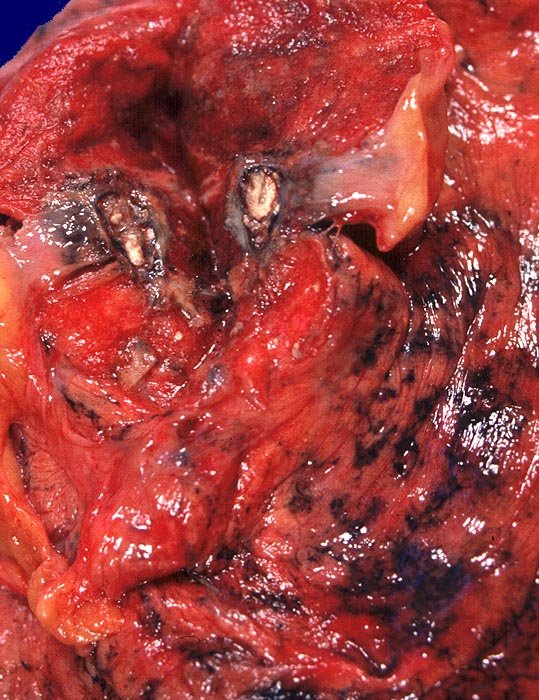

alter tuberkulöser Primärkomplex

Kalkkreideherd im apikalen Oberlappen rechts.

Langjähriger Nikotinabusus. Zungenkarzinom bekannt seit einem Jahr. St.n. kleinzelligem Bronchuskarzinom vor 4 Jahren.

Makroskopie